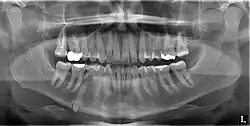

Classifications enable the oral surgeon to determine the difficulty in removal of the impacted tooth. [9] The primary factor determining the difficulty is accessibility, which is determined by adjacent teeth or other structures that impair access or delivery pathway. The majority of classification schemes are based on analysis on a radiograph. The most frequently considered factors are discussed below.

This type of classification is based on the amount of impacted tooth that is covered with the mandibular ramus. It is known as the Pell and Gregory classification, classes 1, 2, and 3.[10]

Relationship of tooth to occlusal plane

The depth of the impacted tooth in relation to the adjacent second molar serves as the foundation for this type of classification. This was also given by Pell and Gregory and is known as the Pell and Gregory A, B, and C classification. Relationship to the occlusal plane A-C classes